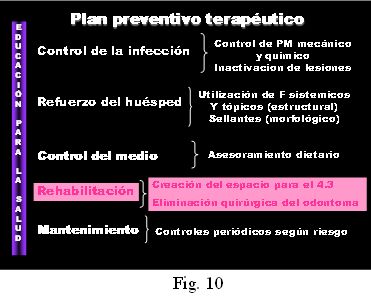

A los 2 meses de instalada la aparatología, se logra el espacio para ubicar correctamente el 4.3 y 4.2 en la arcada y se centra la línea media (Fig. 9), coordinándose en la Sección Quirúrgica de la Cátedra de Odontopediatría, la cirugía correspondiente para la enucleación del Odontoma Compuesto y la exodoncia del canino caduco (8.3). El acto quirúrgico constituye por lo tanto, un elemento más dentro de un plan de tratamiento integral y oportuno (Fig. 10).